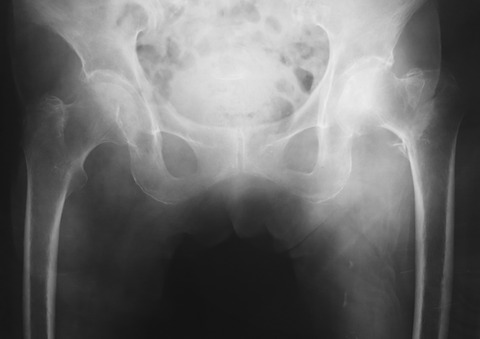

単純X線像上はGarden stage 1でした。